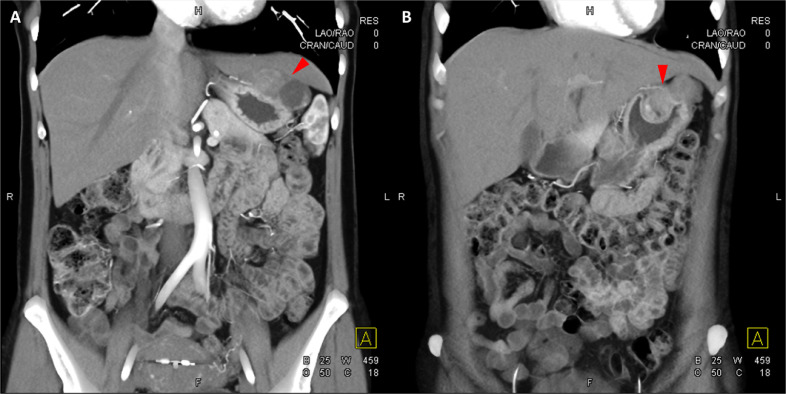

頸部增強 CT 顯示 2 個強烈強化的腫塊。 一個位于頸部右側,位于右側頸內動脈后方的頸動脈間隙中,位于莖突內側,大小為 24 × 24 × 30 mm,頸靜脈橫向移位(圖 1A)。 第二個位于左側頸動脈間隙,在分叉處正上方展開頸外動脈和頸內動脈,尺寸為 15 × 18 × 22 mm(圖 1B)。 影像學檢查結果與右側迷走神經和左側頸動脈體副神經節(jié)瘤一致,與之前的活檢結果一致。

Fig. 1

圖1:右側迷走神經和左側頸動脈體副神經節(jié)瘤。 (A) 軸位增強 CT 顯示右側頸動脈間隙、右側頸內動脈后方(白色箭頭)和莖突內側有強烈強化的腫塊(紅色箭頭)。 (B) 軸位對比增強 CT 顯示左頸動脈間隙有強烈強化的腫塊(紅色箭頭),向后張開頸內動脈(紅色箭頭),向前張開頸外動脈(紅色箭頭)。 (C) 冠狀對比增強 CT 顯示兩個增強腫塊(紅色箭頭)。